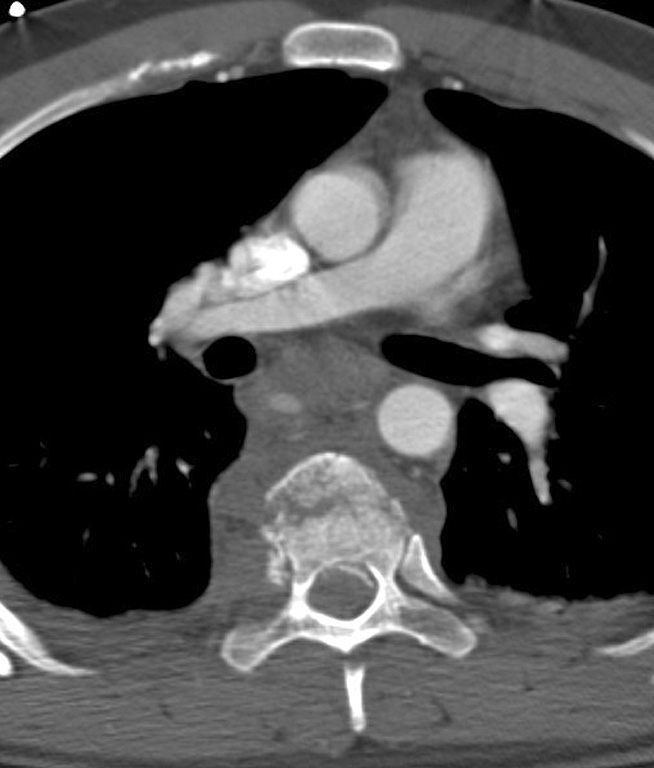

Gallery Blunt Chest Trauma Spine trauma Case 3d

Case 3d